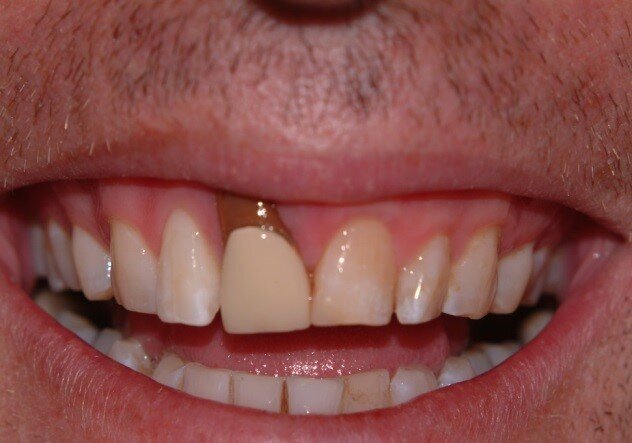

Patient RR was a healthy non-smoking 44 year old male who presented with a complaint of an unaesthetic upper right central incisor with extensive recession showing a large amount of darkened labial root surface. The situation was worsened by a high smile line and a porcelain crown contrasting dramatically with the root colour. He had had periodic swelling at the apical part of the recession over a long period. There was a history of trauma in his teens leading to root canal treatment and a crown, and subsequent apicectomy in his 20s. Clinical examination revealed an otherwise periodontally healthy, well looked-after mouth. (Fig. 1, 2, 3)